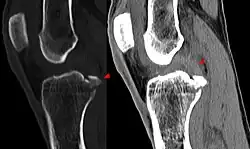

Die Diagnose kann mit bildgebenden Verfahren – namentlich der Magnetresonanztomographie (MRT, „Kernspin“) – bestätigt werden. Dabei ist allerdings zu beachten, dass die Interpretation der MRT in der Diagnostik eines Kreuzbandrisses zu 20 Prozent falsche Diagnosen liefert. Hier kommt es auf die sogenannten Schnittbilder und die geeignete Positionierung des Kniegelenkes bei der MRT-Untersuchung an. Der Radiologe sollte die genaue Vorgeschichte kennen, die zur Verletzung führte, und auch Erfahrung in der Untersuchung eines verletzten Gelenkes haben, um Fehlbeurteilungen zu vermeiden. Im Vergleich zur MRT liegt die Fehlerquote bei dem erheblich einfacher durchzuführenden Lachman-Test bei nur 10 Prozent.[85][86][87][88] Die MRT ist daher in der Regel zur Diagnose eines vorderen Kreuzbandrisses weniger sensitiv und weniger spezifisch als die klinische Befundung durch einen qualifizierten Orthopäden.[89] Das Ergebnis einer MRT hat nur relativ selten einen Einfluss auf die klinische Entscheidungsfindung[90] und sollte keinen Ersatz für eine sorgfältige Anamnese und Palpation darstellen.[15] Mehrere Studien kommen zu dem Schluss, dass eine MRT nur bei komplizierteren unklaren Knieverletzungen – und dabei eher zum Erstellen einer Ausschlussdiagnose[91] – sinnvoll ist.[92][93]

Röntgenaufnahmen leisten keinen unmittelbaren Beitrag zur Diagnosestellung einer Kreuzbandruptur. Beide Kreuzbänder sind – ob gerissen oder nicht – im Röntgenbild nicht sichtbar. Wird dennoch geröntgt, so kann dies der Diagnosestellung von möglichen knöchernen Begleitverletzungen dienen.